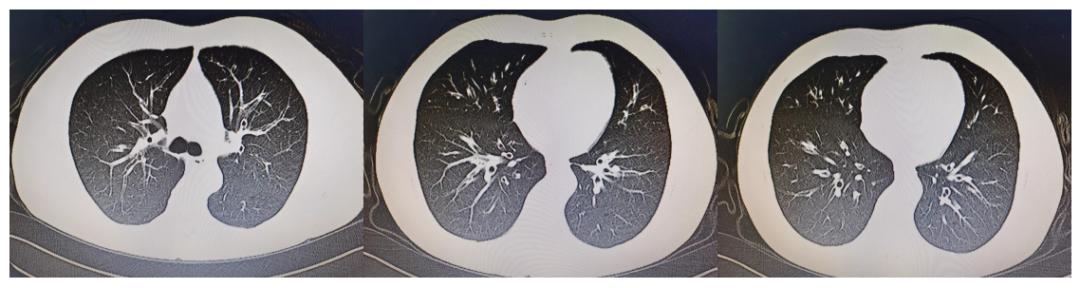

门诊胸部CT:

双肺多发支气管壁增厚,部分管腔内黏液充盈,考虑支气管炎。右肺下叶后基底段散在微小结节。